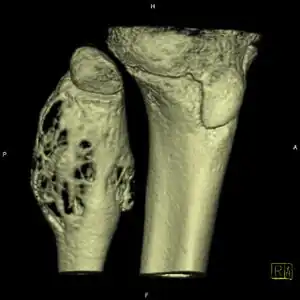

| Aneurysmal bone cyst (fibula, around knee). | |

X-ray and CT scan show lytic expansion lesions with clear borders.[1] Expansion of cortex gives the lesion a balloon-like appearance. Larger lesions may appear septated.[10] MRI reveals fluid levels.[1] Bone scan shows outer radiotracer uptake, with a central dark area.[1]

-

X-ray: ABC large long bone of lower leg near knee -

ABC shoulder -

CT scan: ABC ulna near wrist -

CT scan: ABC fibula -

CT scan: ABC spine -

MRI scan: showing fluid levels -

DSA: ABC of shoulder -

Bone scan: ABC left radius